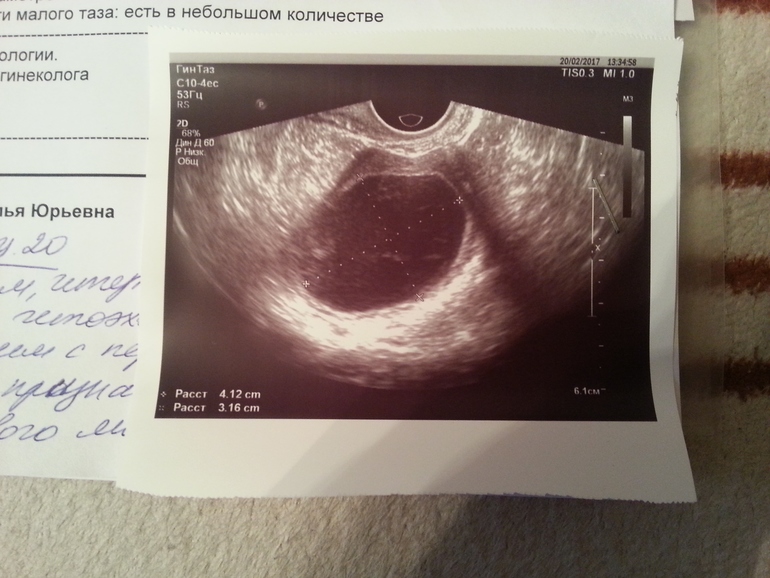

Девочки посмотрите пожалуйста!!!! Где ручкой написано -это сегодняшняя.Я что то не пойму ,была овуляция или нет? Что значит киста желтого тела? С такими значениями не получится забеременеть в этом цикле??? Объясните мне пожалуйста!!!))

Почему нет? Очень даже дк. Это же не фолликулчрная киста, а желтого тела.

Киста жёлтого тела может заблокировать овуляцию в след.цикле,радоваться в принципе нечему,киста жт не так часто при беременности бывает и для 20 дц большеватая даже

Было три Б и во все три Б была киста желтого тела. На беременность никак не повлияло